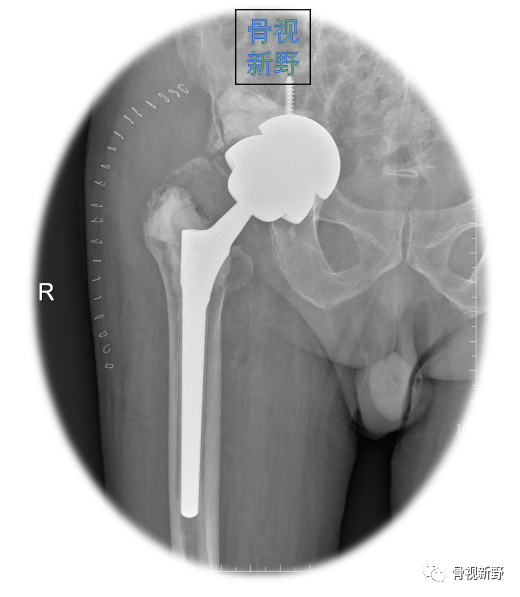

Case 2: Paprosky IIc